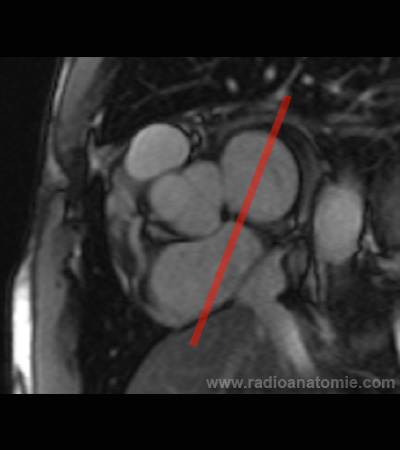

Radioanatomie et plans de coupe en IRM cardiaque

Plan 2 cavités